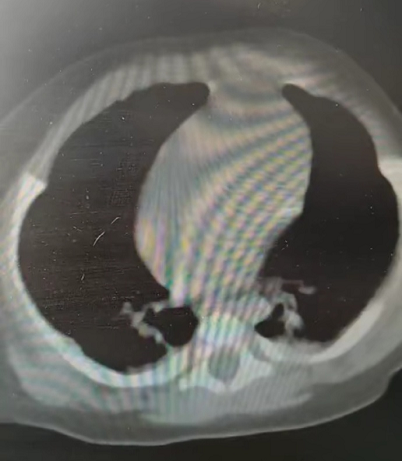

圖片來源:@微創外科雙5槍